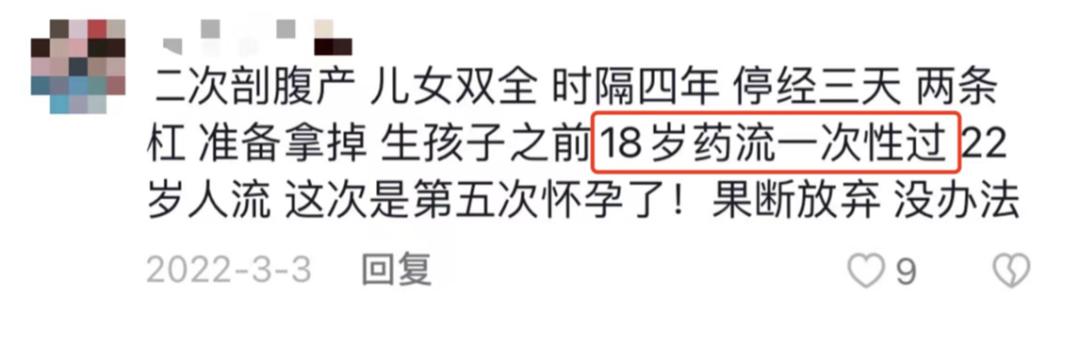

相关的视频下,也有不少人出来“现身说法”。

十八岁做药流、引产几次、高考后“偷尝*果禁**”......在这些简短的文字里,流产,只成为了一次轻飘飘的人生经历。

2015年的数据显示,中国人流手术量连年增长,当年约有1300万的人流手术量,居世界第一。

而这个数字,还不包括约1000万药物流产和在未注册私人诊所做的人流。而且调查显示,接受人流的25岁以下女性约占50%,65%为未婚女性。有54.3%是因未采取任何避孕措施导致意外怀孕,反复人流者也高达50%。